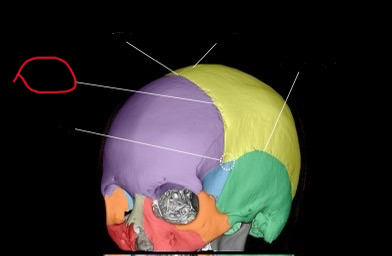

anth 1400 lab exam 1 cranial, skull shit

sphenoid bone (lateral)

also greater wing

frontal bone (lateral)

ethmoid bone (lateral)

also orbital plate

temporal bone (lateral)

occipital bone (lateral)

parietal bone (lateral)

coronal suture (lateral)

pterion

coronal suture (suture)

bregma

sagittal suture

squamosal suture

lambdoid suture